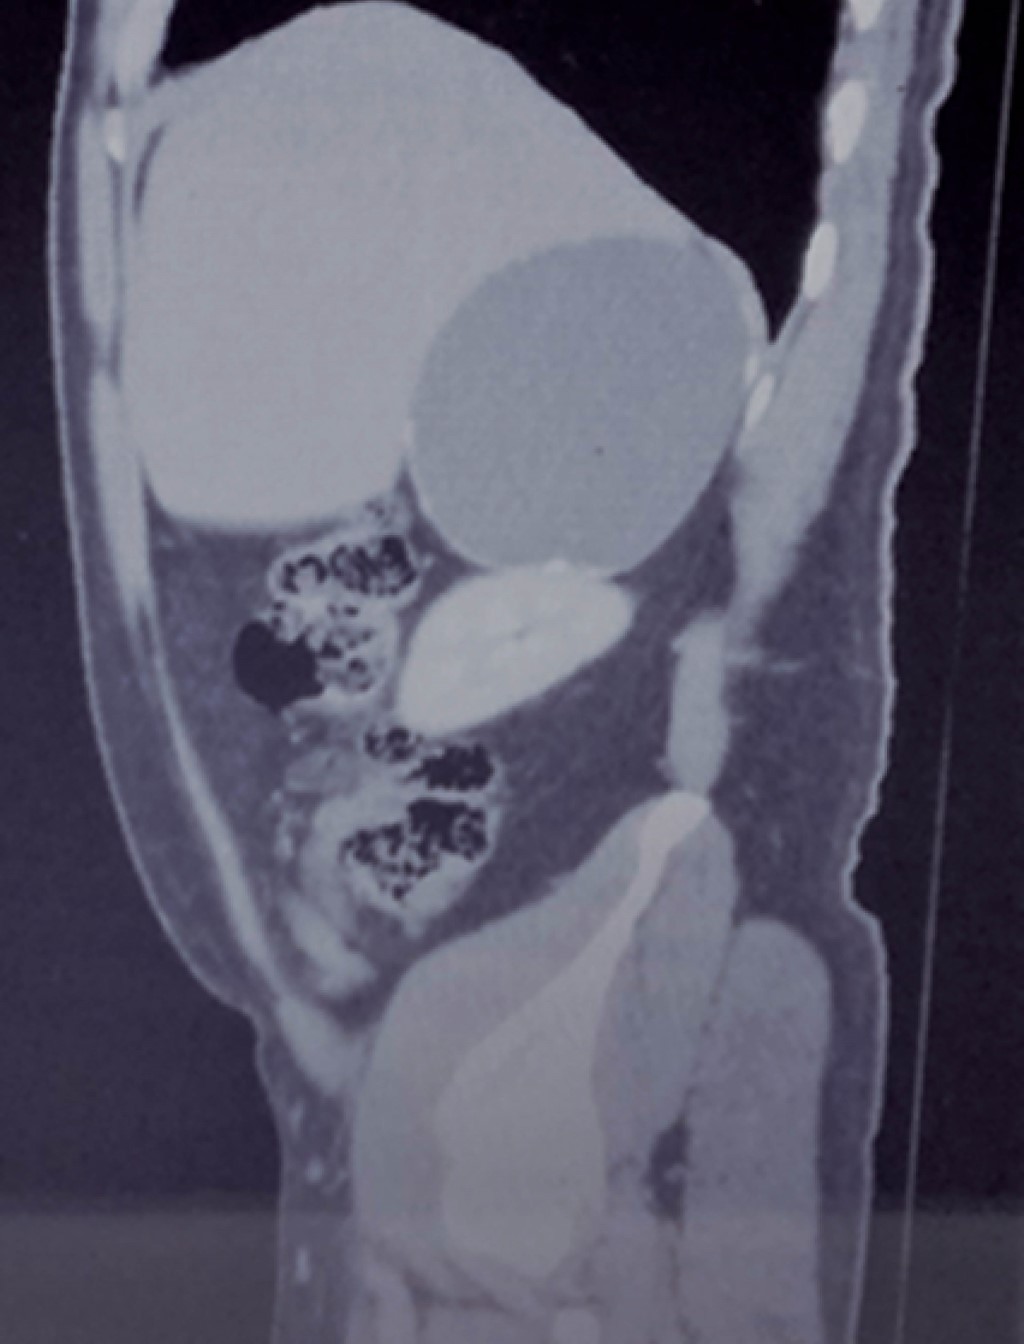

Ultrasonido de marzo reporta hígado de tamaño, forma y situación normales con borde inferior derecho irregular, de ecogenicidad heterogénea por presencia de una masa anecoica de forma redondeada y con bordes bien delimitados, paredes delgadas; sugestivo de quiste simple (Figuras 1 y 2).

Biometría hemática, pruebas de función hepática, renales, TP y TPT de mayo de 2018 normales. No se realiza cortisol, aldosterona, catecolaminas urinarias ni metanefrinas. Tomografía de mayo reporta en glándula suprarrenal derecha imagen hipodensa con diámetros máximos de 101 mm, calcificaciones en su interior con efecto ocupativo y compresivo sobre las estructuras vecinas (Figuras 3, 4, 5 y 6). Completándose su valoración preoperatoria por medicina interna, se programa abordaje quirúrgico anterior abierto y bajo profilaxis antibiótica con ceftriaxona 2 g en dosis única, se realiza incisión subcostal derecha, destechamiento con electrocauterio de quiste suprarrenal derecho de 10 × 9 cm, con adherencias al hígado, contenido de aproximadamente 400 ml de líquido hialino y calcificaciones de alrededor de 20 × 40 mm en su interior. Se coloca drenaje abierto, penrose de ½" (19 mm) en espacio subfrénico ante la sospecha de hemorragia postoperatoria.

Figura 2

Figura 3